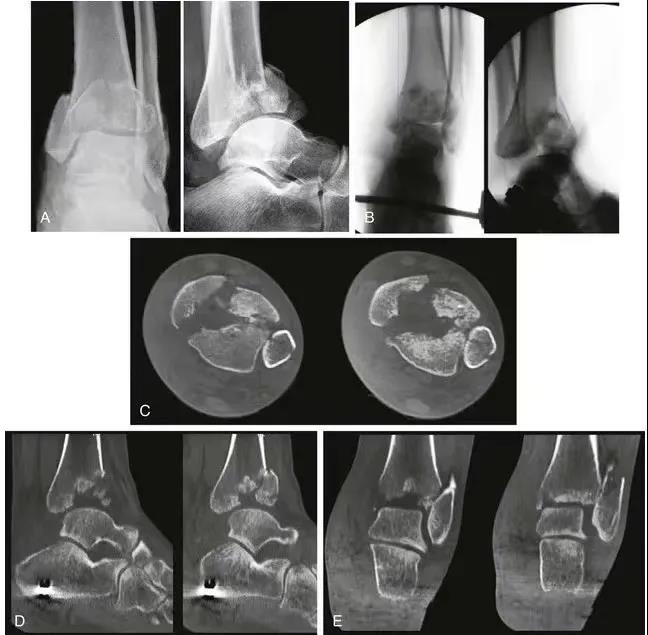

复杂pilon骨折的复位和内固定。A和B,腓骨钢板和跨关节外架的应用。注意关节面的压缩(箭头)。 C,前内侧切口。注意胫前肌腱(黑色箭头)和胫骨干骨折(白色箭头)。 D,关节面的复位。E,使用克氏针复位,然后使用螺钉固定。F应用中和钢板。G和H,术后轴和关节面的前后位X线片和侧位X线片。

一旦关节面重建后,应主要注意干骺端的交界处。当复位长骨骨折时,力线的对齐是主要的功能要求。与关节复位相反,干骺端重建的目标较少依赖于解剖复位,更多依赖于恢复足够的长度和旋转以及力线的对齐。这也可以通过使用外架或股骨牵引器来实现。